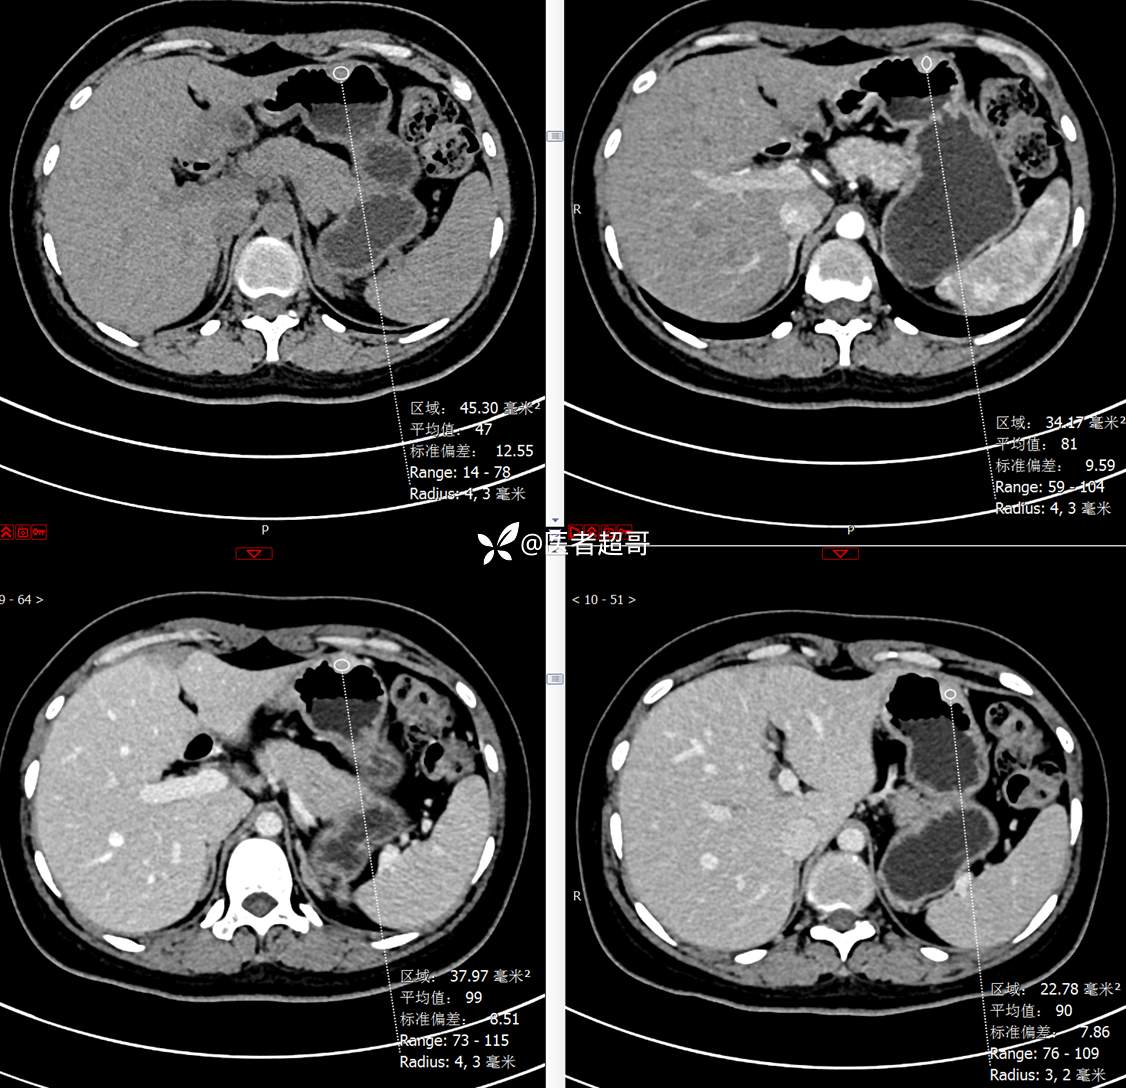

青年男性,恶心、呕吐5年,发现胃肿物3月,有结果,请分析!

主 诉:恶心、呕吐5年,发现胃肿物3月。

现病史:患者5年前无明显原因及诱因出现恶心、呕吐,多于进食后出现,呕吐物为胃内容物,无鲜血及咖啡样物质,偶有空腹痛,无放射痛,无腹泻,无便秘,无黑便、鲜血便,无胸闷、心慌,无头痛、头晕,曾就诊于当地医院口服“消炎药”治疗(具体不详),上述症状反复出现,3月余前就诊于市第二人民医院,行胃肠镜检查:慢性浅表性胃炎、胃体粘膜下占位,后就诊于我院超声内镜检查:胃体肿物,似来源于黏膜下层,今为行进一步治疗来我科就诊,门诊以“胃肿物”收住入院。患者自发病以来,神志清,精神可,饮食一般,睡眠可,大小便正常,体重无明显变化。